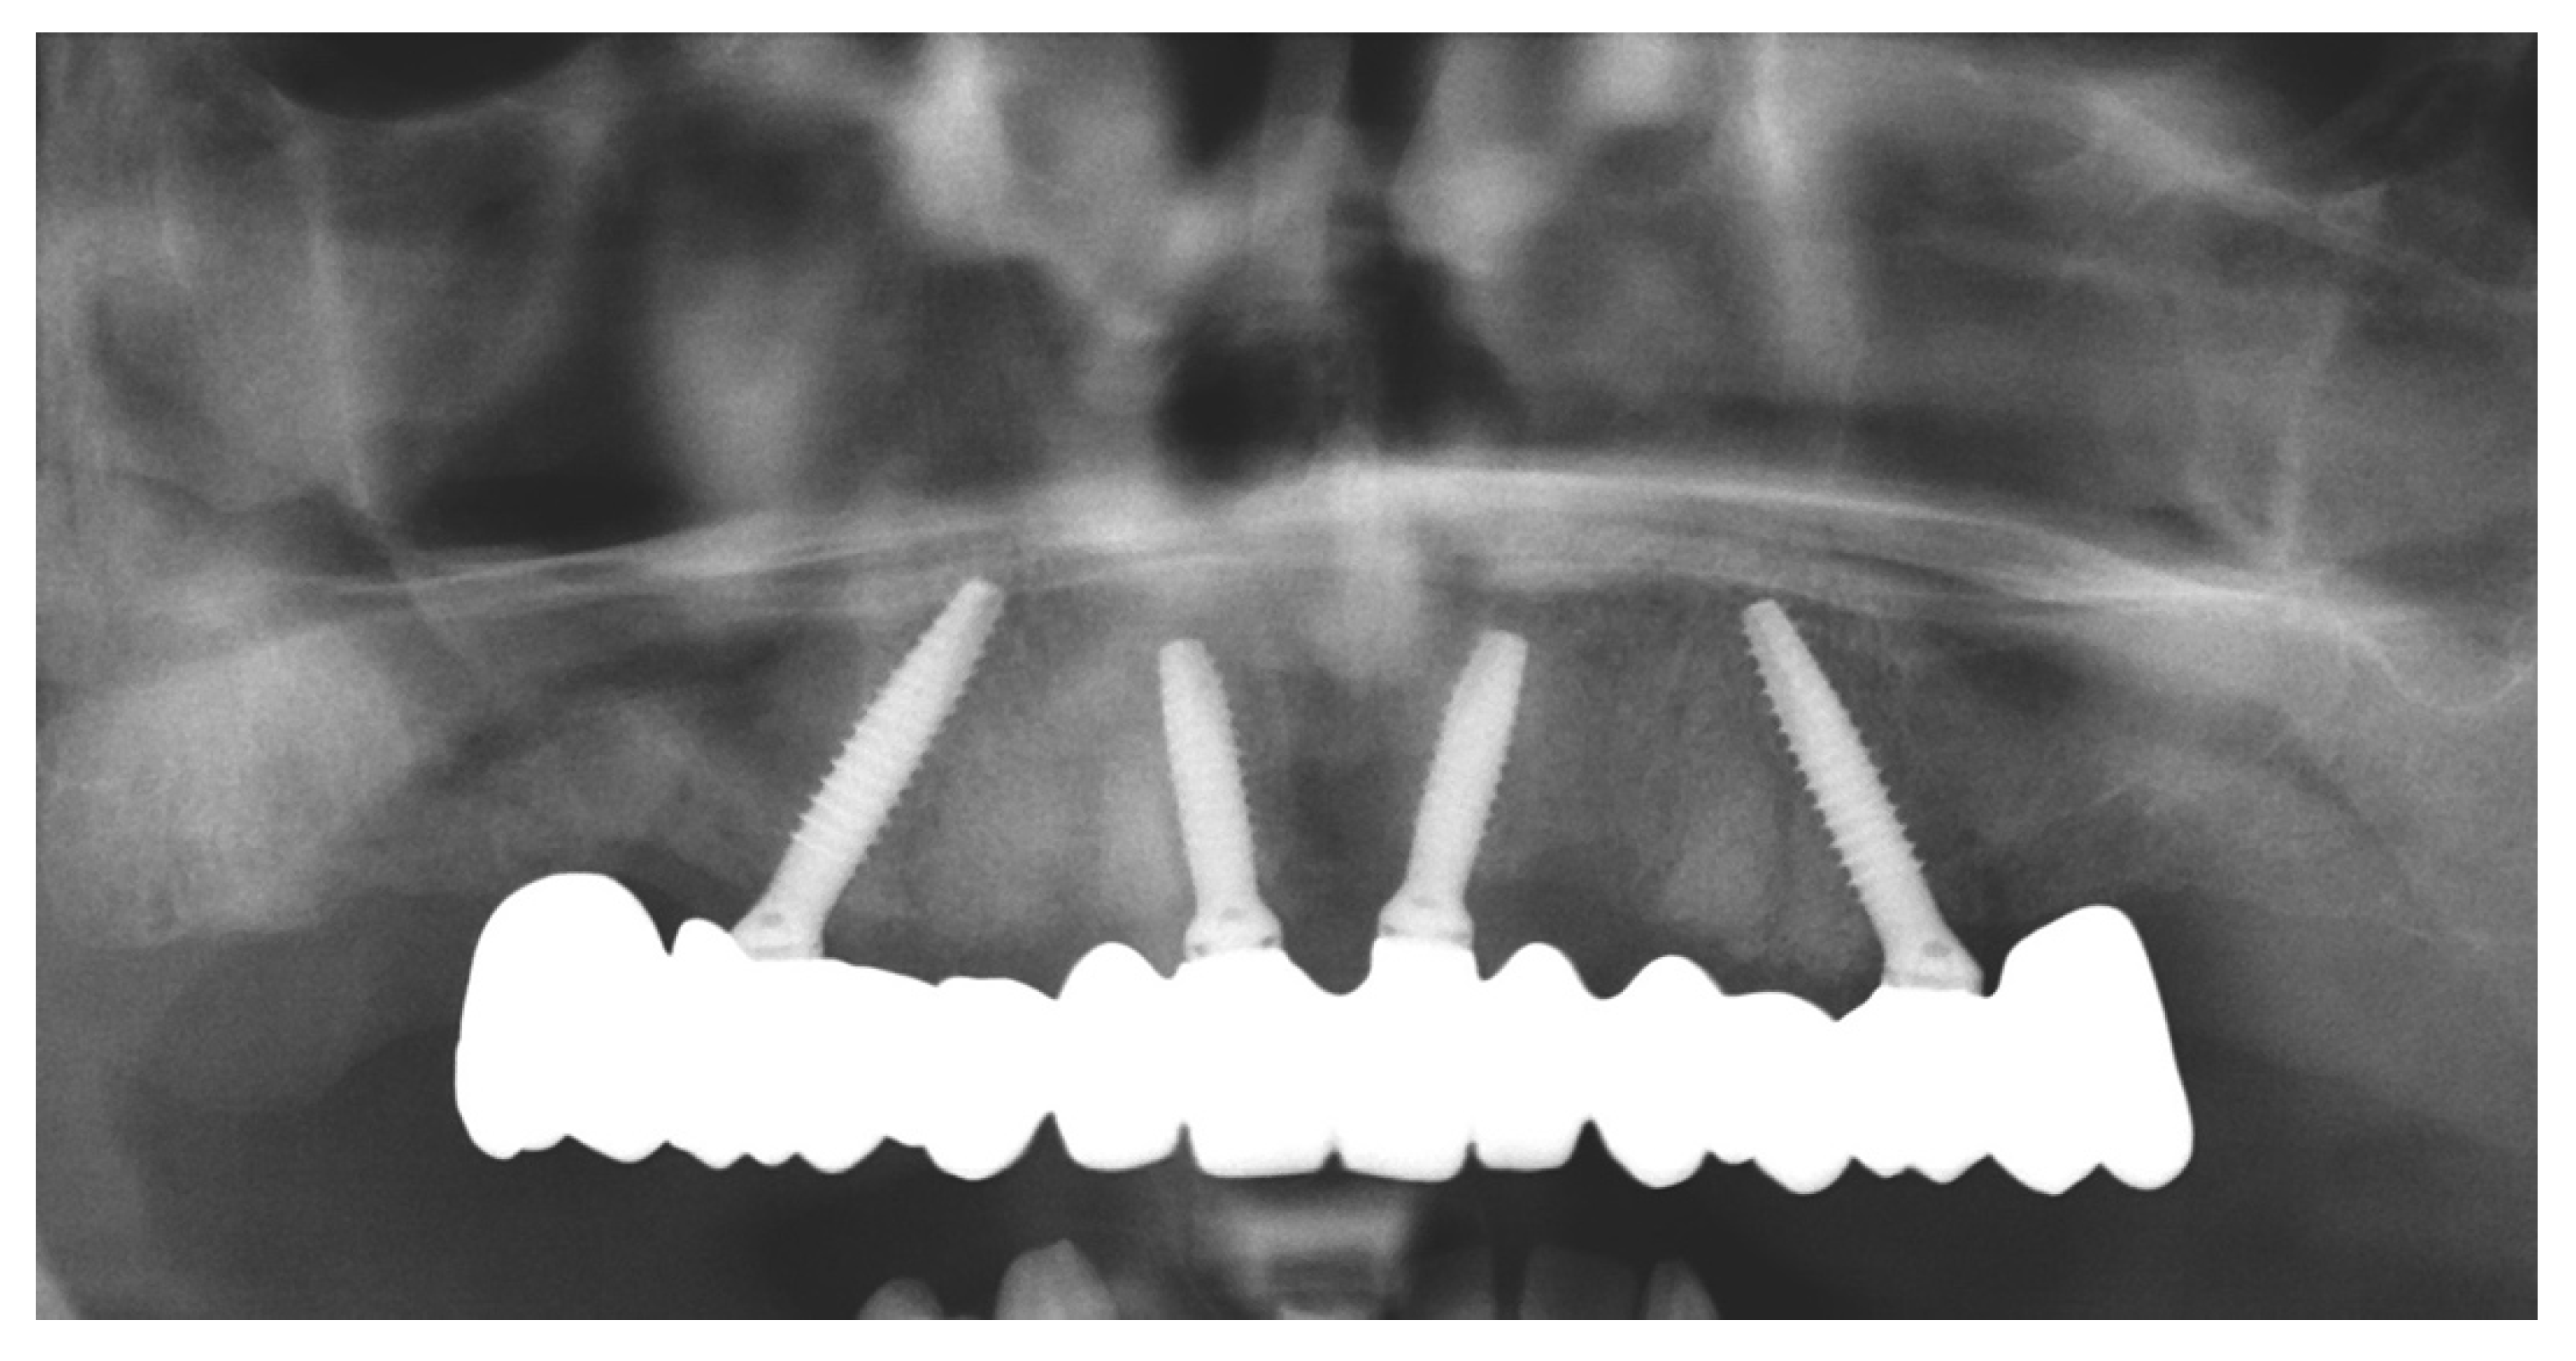

Full Digital Model-Free Maxillary Prosthetic Rehabilitation by Means of One-Piece Implants: A Proof of Concept Clinical Report with Three-Years Follow Up

2. Materials and Methods

- 15: 4 × 15 mm 30°

- 11: 3.5 × 11.5 mm 17°

- 21: 3.5 × 11.5 mm 17°

- 25: 4 × 13 mm 30°